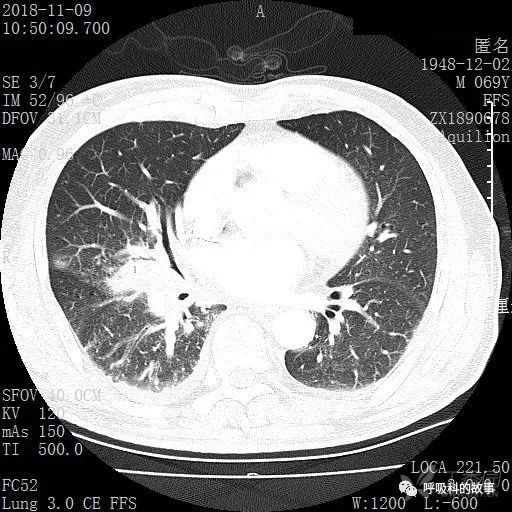

胸部增强CT示右肺门占位伴远端阻塞性肺炎,纵膈、右肺门、右侧颈根部、右侧腋下及肝门部肿大淋巴结。两侧胸腔少量积液。

纵隔窗的增强CT

肺窗CT